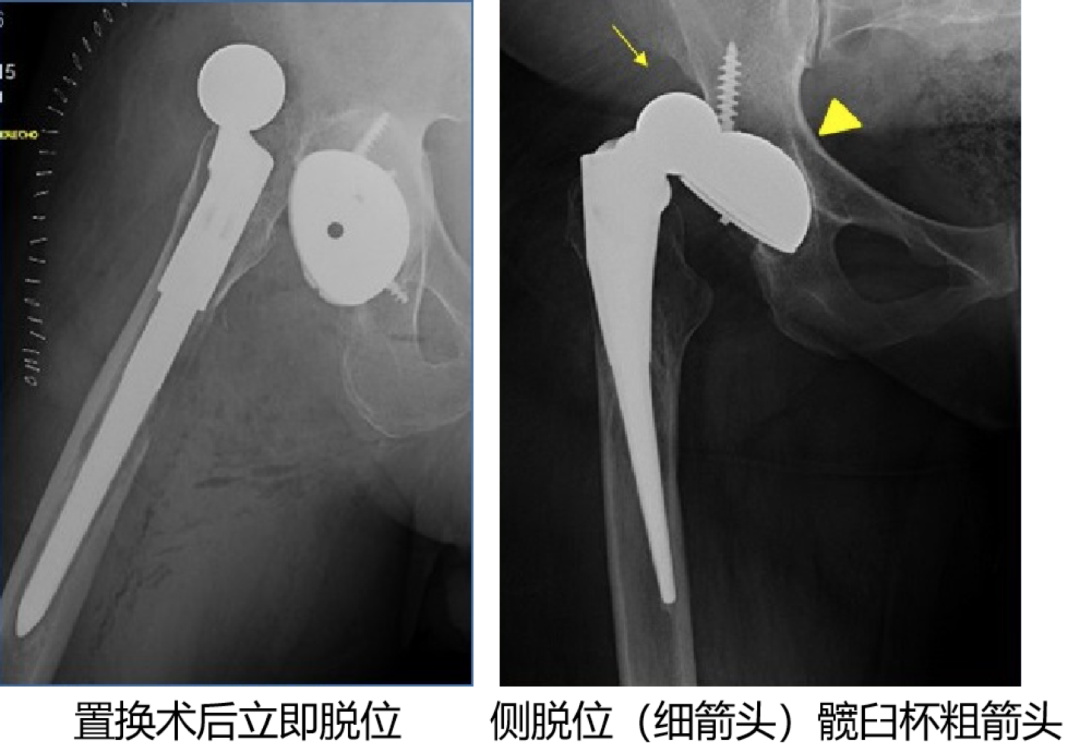

7. 假体失败:

可发生于髋臼或股骨假体。

右侧全髋关节置换术后:聚乙烯磨损,股骨头在髋臼杯内位置不对称(箭头)